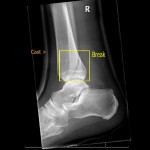

Not to be confused with the title of this blog, adventure racing and adventure challenges have quickly grown into a “sport” that can no longer go unnoticed. When the term is used, it conjures up images of men and women covered in mud, wearing horned hats as if they just left Fred and Barney at a Water Buffalo Lodge meeting. The Spartan Race, Tough Mudder and Warrior Dash are just a few of the events on the ever growing list of neanderthalic activities. The question we have to ask ourselves is, “Are these legitimate races for runners?” In a word, no. I am not going to tell you that these challenges are not fun or physically demanding but they definitely do not qualify as events in which runners should participate. First and most importantly is the risk of injury. Do you really want to jeopardize losing your racing season or worse? If you run 5k’s or marathons you are taking a calculated risk but when confronting an array of dangerous obstacles, your risk for breaking an ankle or tearing a ligament rises substantially.